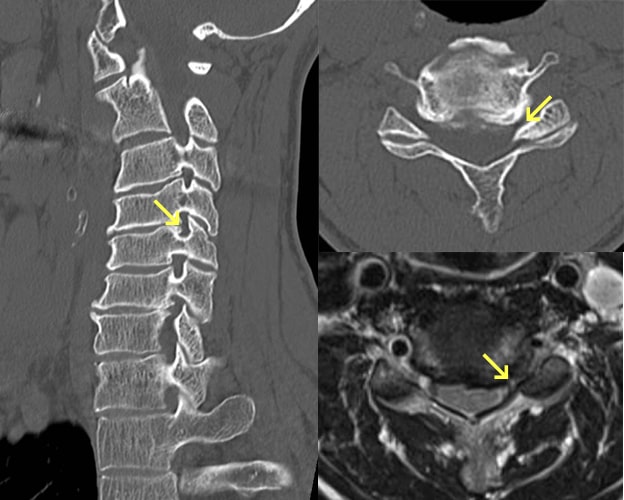

頚椎症

椎間板が年齢とともに変性し、椎間板腔の狭小化、椎体辺縁の骨硬化・骨棘形成、椎間関節の狭小化などの所見が認められるようになります。好発高位は中下位頚椎ですが、高齢者では下位頚椎が可動域を失うことで上位の椎間にストレスが集中するため、C3・4椎間に病変を認めることも多いです。頚椎症により椎間孔および脊柱管が狭窄し神経症状を引き起こします。主な症状は頚椎症そのものによる頚肩部の疼痛、運動制限のほか、神経根や脊髄が圧迫されると痺れや痛み、麻痺などの神経症状が出現します。まずは頚椎の安静を目的に頚椎カラーを使用したり、疼痛に対しては、消炎鎮痛剤の服用、温熱療法や理学療法などが行われます。

頚椎症性脊髄症

ボタンのかけ外し、お箸の使用、書字が不器用になったり、歩行で脚がもつれるような感じや手足のしびれも出てきます。比較的若い方であれば、かけ足やケンケンをしにくくなるなどの軽度の症状を自覚できますが、高齢者では気づくのが遅れる場合があります。転倒などの軽微な外傷で四肢麻痺(脊髄損傷)になる危険性がありますので、転倒しないように注意します。一般的に日常生活に支障があるような手指巧緻運動障害や痙性歩行障害、神経因性膀胱などが見られるようになれば手術的治療が選択されます。